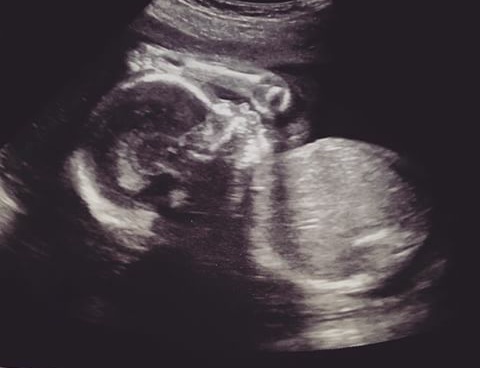

Узи 31-32 недели. Все хорошо?

Результаты: УЗИ, КТГ, доплера, скринингаВес малышки - 1480 грамм (не много?), лежит головкой вниз, воды в норме, плацента 1-2 степени зрелости. Внутренний зев закрыт - угрозы преждевременных нет.